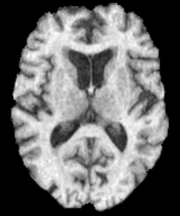

where 𝒙=(x,y,z)𝒙𝑥𝑦𝑧\boldsymbol{x}=(x,y,z) are the spatial coordinates and mg(𝒙)subscript𝑚𝑔𝒙m_{g}(\boldsymbol{x}), mw(𝒙)subscript𝑚𝑤𝒙m_{w}(\boldsymbol{x}) and mf(𝒙)subscript𝑚𝑓𝒙m_{f}(\boldsymbol{x}) denote the gray matter, white matter and CSF probability maps, respectively. These probability maps are obtained from binary segmentation labels for each tissue type of a healthy brain MRI scan.222In a pre-processing step, the binary labels are smoothed and re-scaled to probabilities. Our data d(𝒙)𝑑𝒙d(\boldsymbol{x}) is derived from actual patient MRI tumor segmentations.333We assign d(𝒙)=1𝑑𝒙1d(\boldsymbol{x})=1 to the voxels that have been identified as tumor. More complex scenarios are possible, for example see [5], which uses apparent diffusion coefficient (ADC) values to identify tumor tissue. Figure 1 shows an example of a healthy brain MRI scan (and its associated segmentation) and a patient brain MRI scan (and its associated tumor segmentation). As we discussed the healthy patient brain scan is rarely available in practice. There have been many approaches to address this, such as using a statistical average of many individual brains or image registration methods to approximate the healthy patient brain (see [56] for details). For the most part of this paper, we assume that the healthy patient brain segmentation is given. For our test on an actual clinical scan, we use an atlas-based segmentation in §4.7.

Refer to caption

(a)

(b)

(c)

(d)

Fig. 1: Imaging data which show an axial slice of (a) healthy T1 MRI scan, (b) segmentation of the healthy brain into white matter (white), gray matter (light gray), and cerebrospinal fluid-filled ventricles (dark gray), (c) patient T1 MRI scan diagnosed with glioblastoma, and (d) segmentation of the patient tumor sub-structures into enhancing tumor (white), necrotic tumor (dark gray), and edema (light gray). The patient scan and segmentation are taken from the 2018 Multimodal Brain Tumor Segmentation challenge training dataset [1], while the healthy brain scan and segmentation are obtained from the GLISTR dataset [20]. In our formulation, we assume the tumor core (enhancing and necrotic tumor) to be the tumor segmentation.